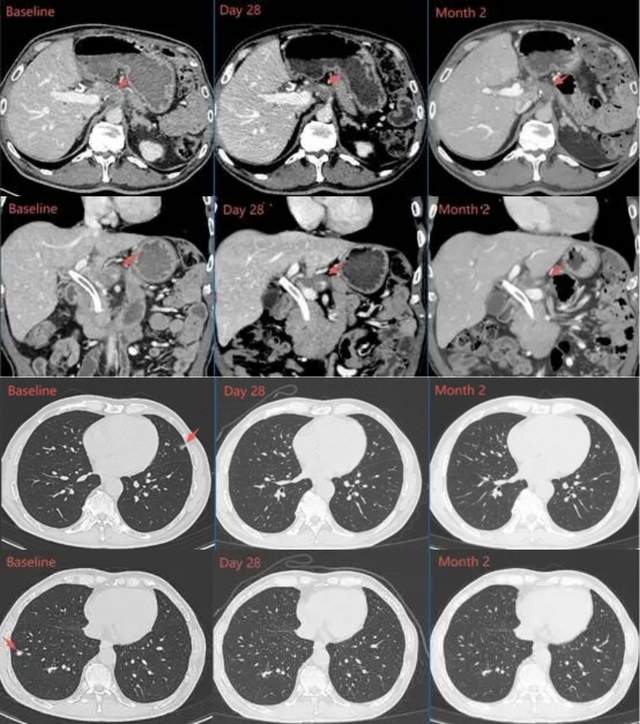

该患者为62岁男性,患有晚期胰腺导管腺癌,在经历三线标准治疗后均无效,基因检测确认其肿瘤存在KRAS G12V突变,于是接受IX001 TCR-T细胞输注。

在接受TCR-T细胞输注后,该患者肿瘤标志物CA19-9在28天内从889U/mL降至正常范围,1个月的复查显示肝门区靶病灶明显缩小、肺部靶病灶基本完全消失,靶病灶直径之和从基线期的67mm缩小至43mm(下降35.8%),达到部分缓解(PR);两个月时病灶进一步缩小至47.8%,持续部分缓解状态。